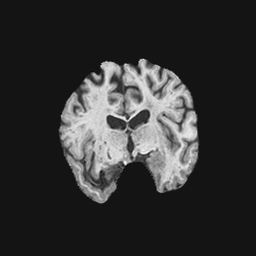

Exp. 1: Segmented adult brain data is used to evaluate our network’s regression performance with known ground truth Tisubscript𝑇𝑖T_{i}. 85 brains from the ADNI data set[1] were randomly selected; 70 brains for ΩtrainsubscriptΩ𝑡𝑟𝑎𝑖𝑛\Omega_{train} and 15 brains for ΩvalidationsubscriptΩ𝑣𝑎𝑙𝑖𝑑𝑎𝑡𝑖𝑜𝑛\Omega_{validation}. Fig. 2 shows an example slice of the ground truth and the reconstructed ΩΩ\Omega.

Figure 2: Example slice from the segmented adult brain MRI data set (a); reconstruction from 300 ωisubscript𝜔𝑖\omega_{i} based on SVRNet regression without SVR (b); SVR initialised with SVRNet predictions after eight iterations of SVR (c). Note that SVRNet (b) predicts individual slice transformations only from image intensities without any initial world co-ordinates of the sampled slice. (d) shows the achieved PSNR in dB when comparing the volumes of (b) and (c) to (a).

Reconstructing from Ti^^subscript𝑇𝑖\hat{T_{i}} initialisation without SVR yields a PSNR of 23.7 ±plus-or-minus\pm 1.09; with subsequent SVR the PSNR increases to 29.5±plus-or-minus\pm2.43 when tested on 15 randomly selected test volumes after four iterations of SVR.